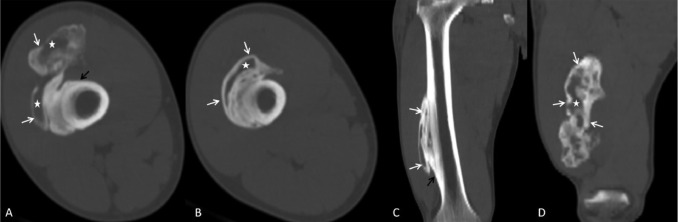

Tomografía computarizada (TC): la confirmación definitiva

La TC es superior a la RM para demostrar la presencia de hueso maduro y el patrón de osificación periférica. En una lesión madura, se observa claramente una corteza ósea periférica que rodea un centro de densidad similar a la médula ósea o al tejido fibroso. Además, la TC permite descartar la continuidad con el hueso adyacente, lo que ayuda a diferenciarla de tumores óseos yuxtacorticales.

Recomendación: ante la sospecha de MO/OH, si la radiografía no es concluyente, la TC es la técnica de elección para confirmar el diagnóstico y evitar la realización de una biopsia innecesaria.